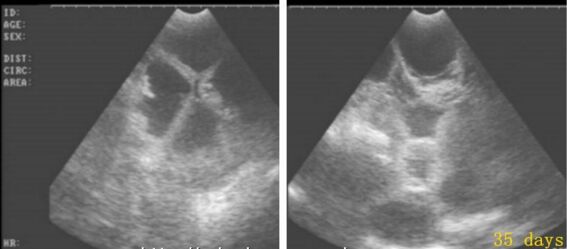

3、B超检测

B超检测早孕的时间一般是在月经推迟一周左右可以去医院做B超检查看是否怀孕,如果在B超下能看到妊娠光环就说明怀孕了。